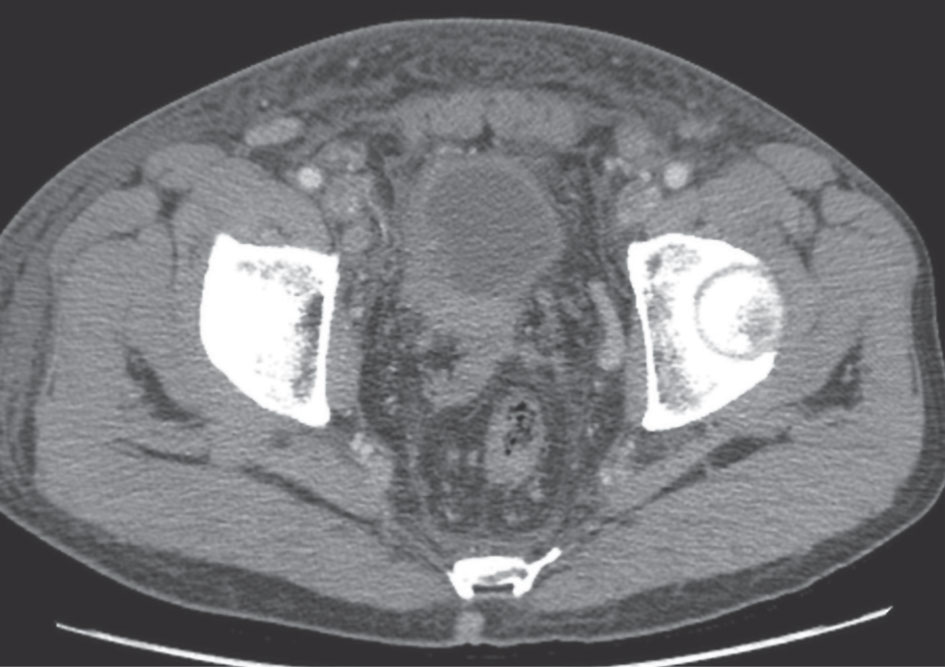

ج- التصوير المقطعي المحوسب والتصوير بالمرنان :CT scan and MRI تصل فيهما نسبة الدقة في كشف الورم وانتشاراته حتى 80-90%؛ ولاسيما فيما يتعلق بإصابة العقد اللمفاوية التي تكون أكبر من 1سم (الشكل 9).

![]() |

الشكل (9) تصوير طبقي محوسب يُظهر ورم مثانة مرتشحاً في الجدر على الـ .CT |